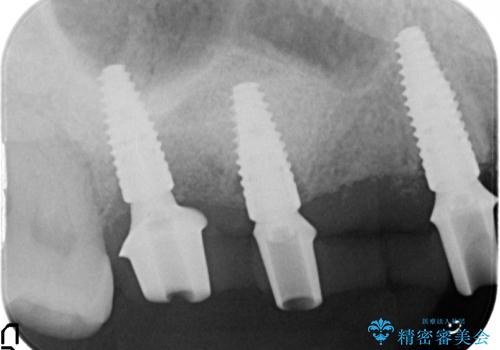

- 120万円(ストローマンインプラント×3・骨造成・チタンカスタムアバットメント×3・フルジルコニアクラウン×5)費用は治療当時の料金となります

連続した多数の歯の機能・審美回復にブリッジは設計上治療の手段になり得ない場合があります。

残された選択肢は入れ歯・インプラントになりますが審美性・咬合機能の回復度・快適さ・残存歯への負担は雲泥の差となります。